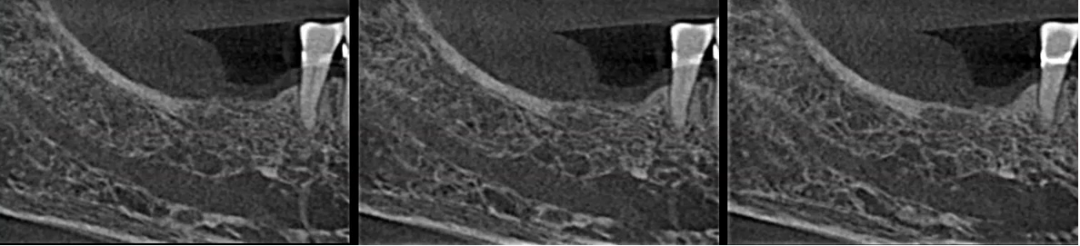

进一步检查:口腔CBCT的应用

36、46根管评估,45根尖颏孔鉴别诊断

曲面断层片怎么看口腔精读 | 一次性教你看懂曲面断层片!_https://www.jmylbn.com_新闻资讯_第48张

曲面断层片怎么看口腔精读 | 一次性教你看懂曲面断层片!_https://www.jmylbn.com_新闻资讯_第49张

42根尖区低密度影鉴别诊断

曲面断层片怎么看口腔精读 | 一次性教你看懂曲面断层片!_https://www.jmylbn.com_新闻资讯_第50张

38根尖区高密度影鉴别诊断

曲面断层片怎么看口腔精读 | 一次性教你看懂曲面断层片!_https://www.jmylbn.com_新闻资讯_第51张